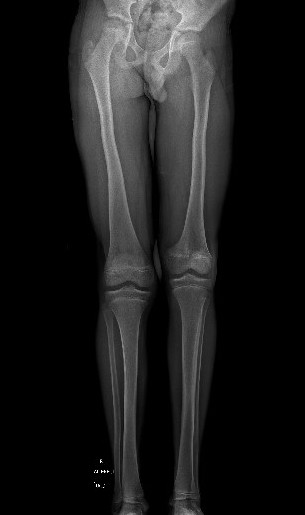

Complete growth arrest / Leg length discrepancy

SH1SH1LLD

Monitor 6 monthly

- plot short and long leg lengths on Mosely chart

- distal femur contributes 9 mm / year

LLDLLD

Manage LLD as per predicted difference

- contralateral femoral epiphysiodesis +/- femoral lengthening